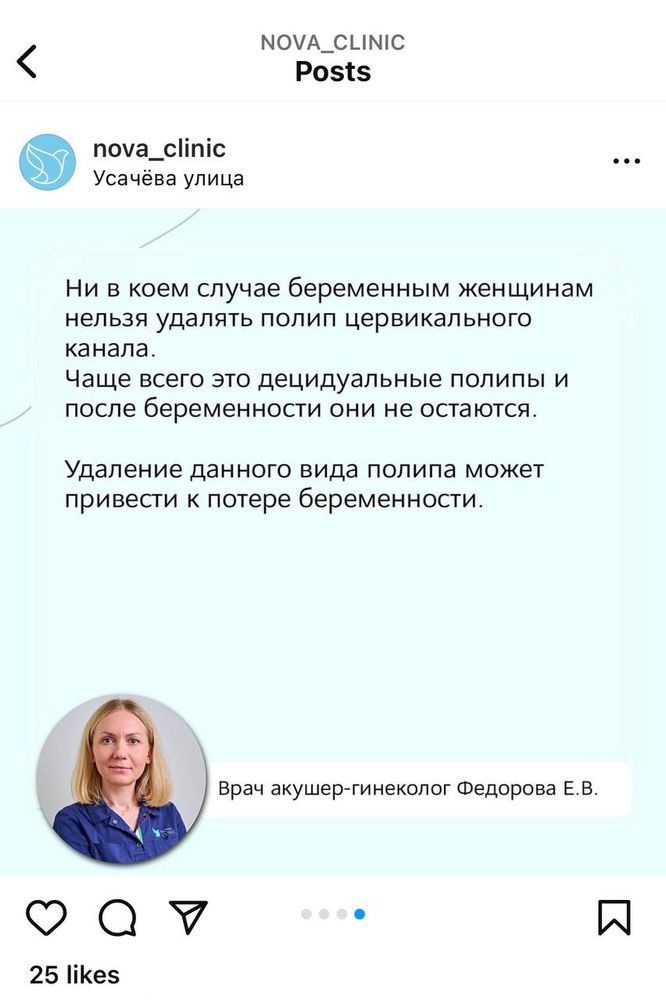

В общем у меня 14н и 3д сходила на узи посмотреть карапуза, с ним слава богу все хорошо, НО обнаружили полип цервикального канала и внутренний зев приоткрыт из-за него! Не кровит, ничего не беспокоит! У кого так было? Чем все у вас закончило?